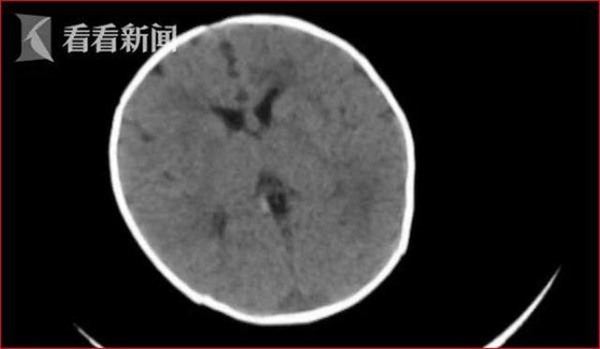

Bác sĩ đã chụp cắt lớp vi tính bộ não của đứa trẻ, phát hiện thấy có một số vi mạch trong não bị xuất huyết.